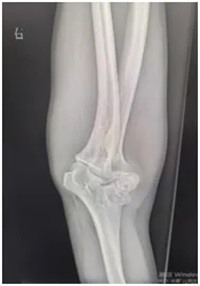

刘师傅赶忙来到郑州大学第五附属医院骨科一病区就诊。接诊医生为他安排了肘关节X线和上肢肌电图检查:

X线显示:肘关节存在明显畸形改变;

X线复查显示:钢板固定位置十分合适,骨头对位良好;